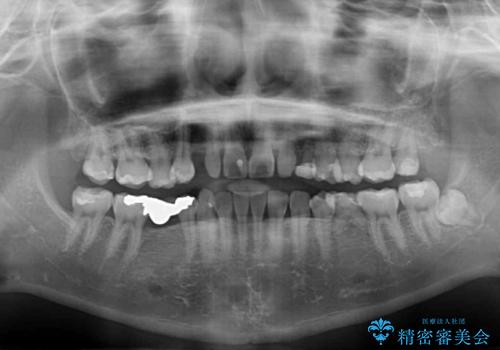

欠損と残存乳歯 矯正治療とインプラント治療

- 残存した乳歯や歯の欠損、歯並びを気にして来院された患者様です。

乳歯を残した状態は予後がよくないこと、矯正治療と補綴治療を総合的に進めていきたいとのことで、インビザラインによる矯正治療とインプラント補綴治療を並行して進めていくこととしました。